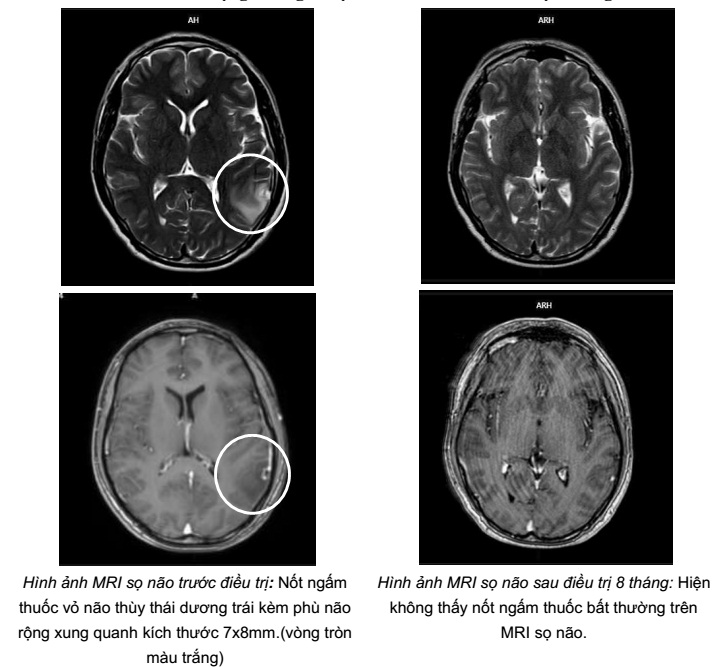

- Cộng hưởng từ sọ não:

Hình ảnh nốt ngấm thuốc vỏ não thùy thái dương trái kèm phù não rộng xung quanh kích thước 7x8mm (vòng tròn màu trắng) do di căn

So sánh hình ảnh cộng hưởng từ sọ não trước và sau điều trị 8 tháng

Sau 9 tháng điều trị: U phổi giảm kích thước, hạch trung thất không còn, tổn thương di căn não đơn ổ biến mất, chất chỉ điểm khối u CEA, Cyfra 21-1 giảm về giới hạn bình thường. Bệnh nhân không gặp tác dụng phụ đáng kể nào trong quá trình điều trị.